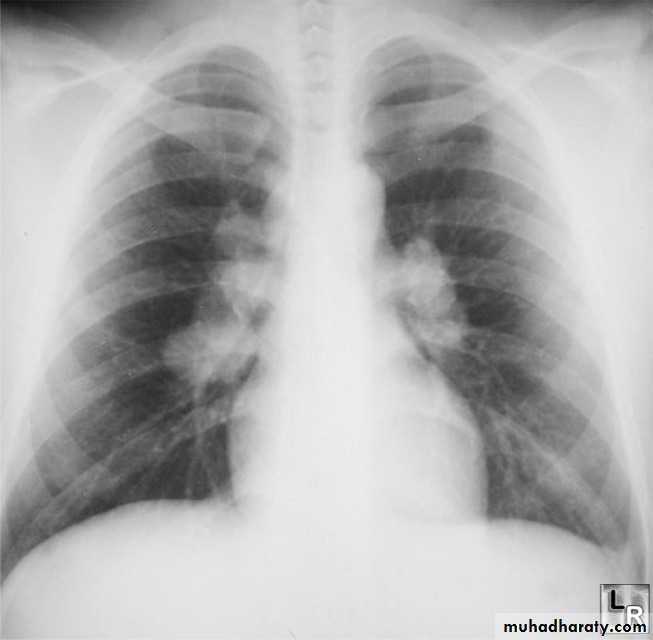

Pulmonary arterial hypertension results from elevation of the resistance in the pulmonary arterial bed, usually at the arteriolar level. It is characterized radiographically by enlargement of the pulmonary trunk and right and left main pulmonary arteries with disproportionately small peripheral vessels This has been referred to as "pruning" of the pulmonary arteries

So the Plain radiograph

elevated cardiac apex due to right ventricular hypertrophy

enlarged right atrium

prominent pulmonary outflow tract

enlarged pulmonary arteries

pruning of peripheral pulmonary vessels